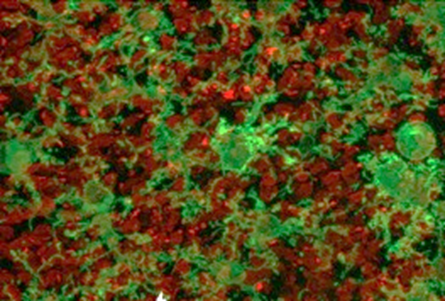

Immagine 1: micrografia a fluorescenza di una sezione della retina esterna. In rosso: i coni